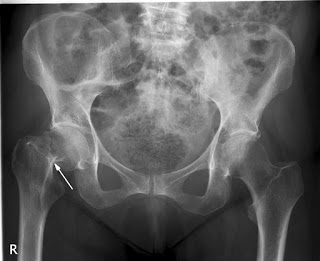

No se está tratando bien la osteoporosis luego de la fractura de cadera

Un estudio encuentra que menos del 10% de los pacientes había iniciado tratamiento para osteoporosis luego de 6 meses de la fractura, a pesar de los beneficios demostrados de los fármacos en esta indicación. JAMA Network Open, 20 de julio de 2018